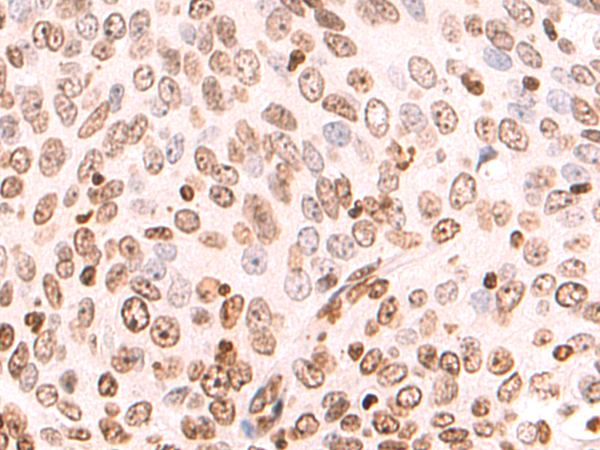

分类: 科研抗体货号: P12837别名: ZAP; ZC3H2; ARTD13; PARP13; FLB6421; ZC3HDC2应用: IHC反应种属: Human